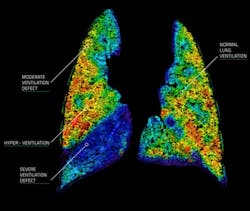

Real-time four-dimensional lung function imaging